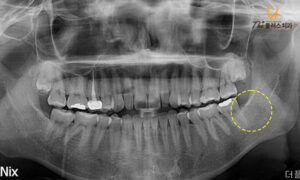

충분한 상담 후 사랑니 발치를 진행하였고,

깔끔하게 발치가 완료된 모습입니다.

사랑니 치아의 뿌리가 많이 휘어있었고,

신경과 매우 가까운 상태였으나

신경의 손상이 없이,

뿌리와 잔여물 없이 깔끔하게 제거가 되었습니다.

한동안은 사랑니 부위가 비어 있으나

그 부위에는 시간이 지나 조직이

채워짐을 기대해볼 수 있습니다.